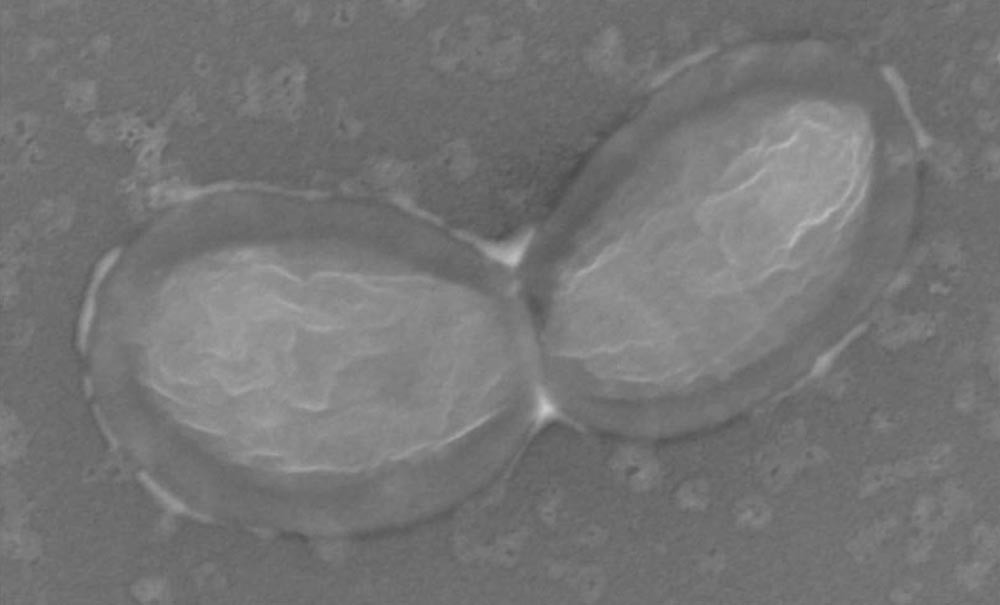

Les inflammations de la cavité orale sont liées à des déséquilibres de la flore de la cavité orale (dysbioses du microbiote), sous l’effet de l’alimentation mais aussi la prise orale ou générale de certains médicaments et de tabac. La dysbiose cause l’inflammation directement en dégradant la muqueuse par les activités enzymatiques cytolytiques ou indirectement par des activités immunomodulatrices. Notre équipe de recherche contribue à l’étude du microbiote et des dysbioses, qui associent à certains eucaryotes unicellulaires (amibes), des bactéries anaérobies et des Archaea méthanogènes (qui fabriquent du méthane, également en anaérobiose) telles que Methanobrevibacter oralis et Methanobrevibacter massiliense (car découverte à Marseille), de culture difficile, donc mieux détectées par des tests de biologie moléculaire par PCR et ses dérivés à température constante isotherme (LAMP). En effet, des études ont suggéré un lien entre les Archaea méthanogènes, l’infection endodontique et les maladies parodontales. Plus récemment encore, notre équipe a découvert une toute petite Archaea, Nanopusillus massiliensis coisolée avec l’Archaea méthanogène M. oralis : ces données nouvelles permettent de mieux comprendre l’histoire naturelle des parodontites incluant les péri-implantites, et d’imaginer des solutions de dépistage biologique maintenant disponibles pour les praticiens, fondant une approche thérapeutique raisonnée basée sur les évidences.